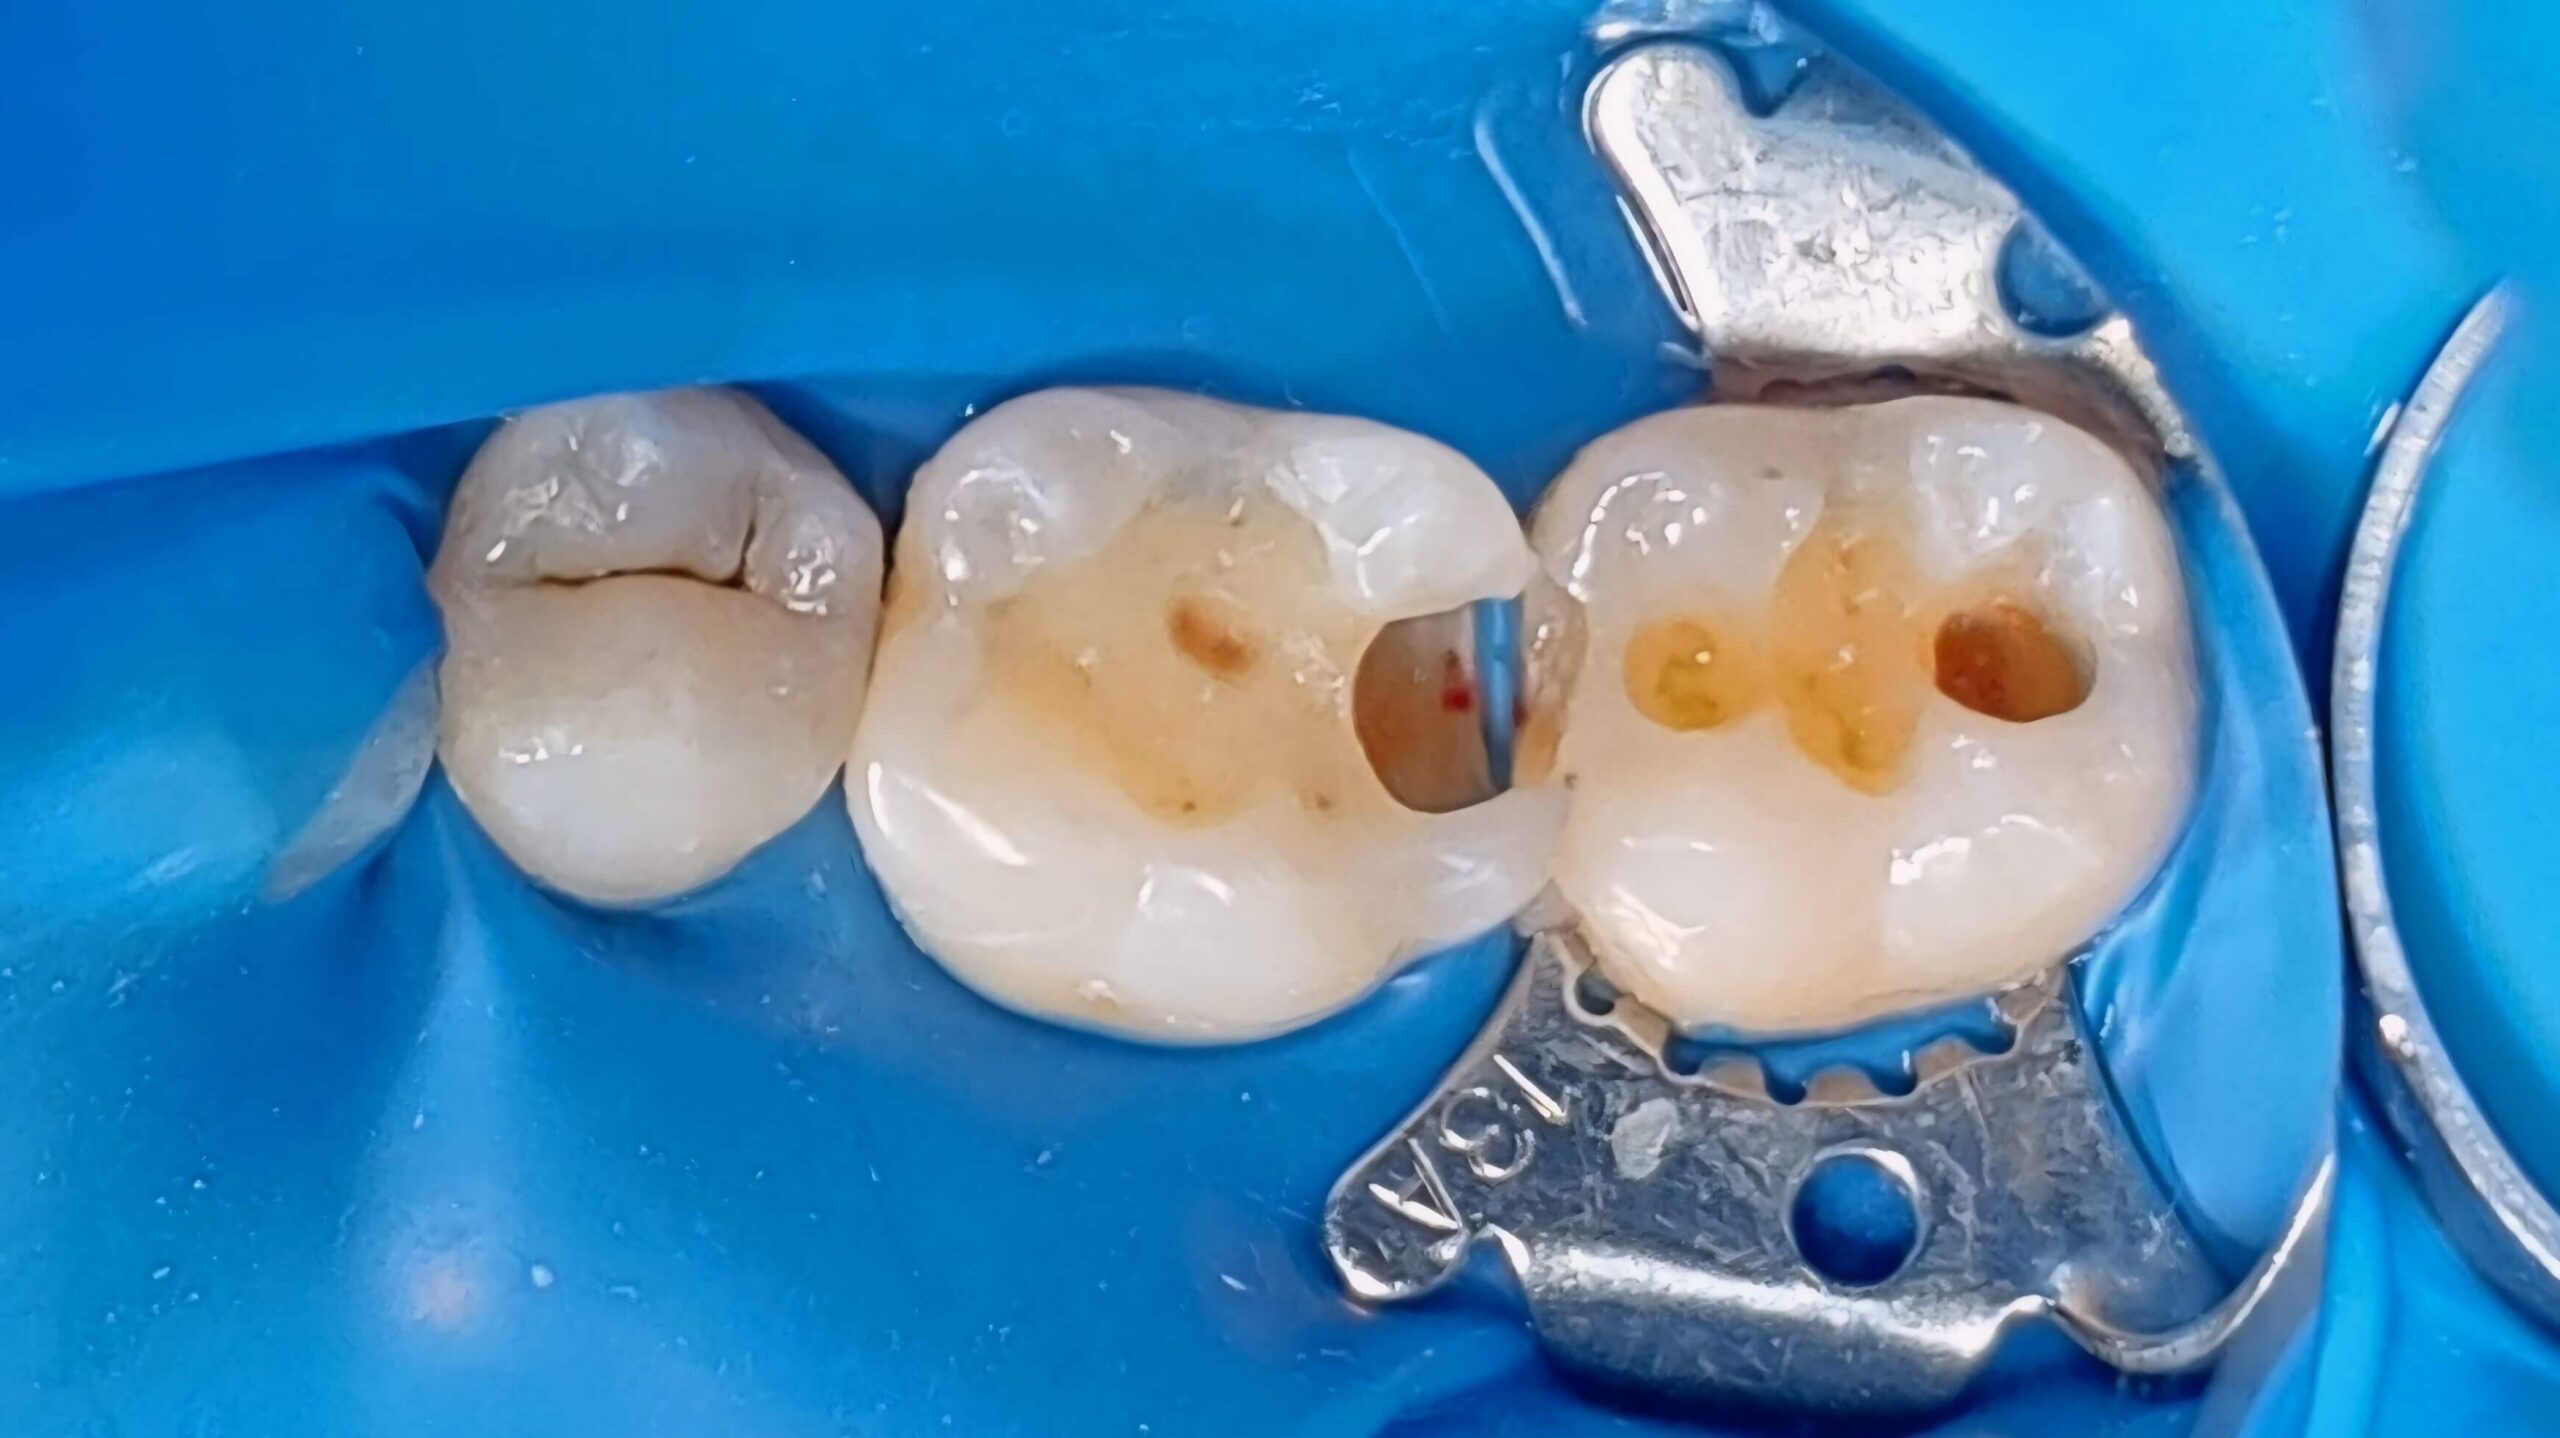

Художня реставрація зубів з використанням композитних матеріалів

Вихідна ситуація: дискомфорт під час жування та помітне пошкодження жувальної поверхні молярів. Оглянувши ротову порожнину пацієнта, ми виявили каріозну порожнину на жувальній поверхні зуба. Пролікувавши карієс ми запропонували естетичну реставрацію зуба з використанням композитних матеріалів. Як результат, пацієнт отримав відновлену поверхню зуба, яка не відрізняється за функціональністю та естетикою від природної.

Категорія: Художня реставрація